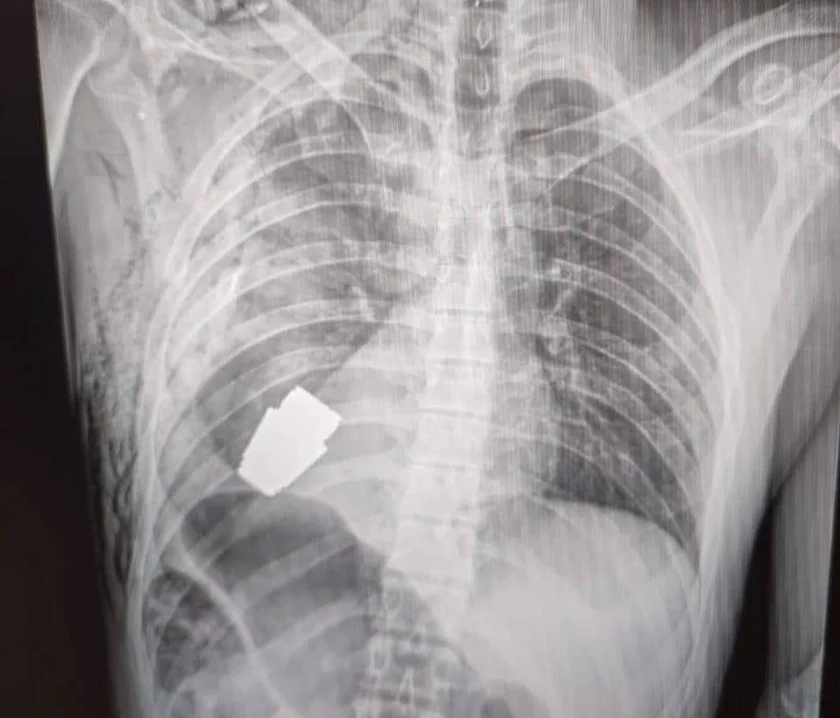

К публикации в том числе прикреплены фотографии с рентгеновским снимком, на котором видна та самая граната рядом с сердцем солдата, и хирургом, который держит в руках извлеченный окровавленный боеприпас уже после проведения операции.

9 января командование медицинских сил ВСУ в своем фейсбуке сообщило о проведении хирургической операции по извлечению из груди своего раненого военнослужащего неразорвавшейся гранаты ВОГ (Выстрел Осколочный Гранатометный — боеприпас длиной 4 см, который выстреливается из гранатомета и может пролететь около 400 м).